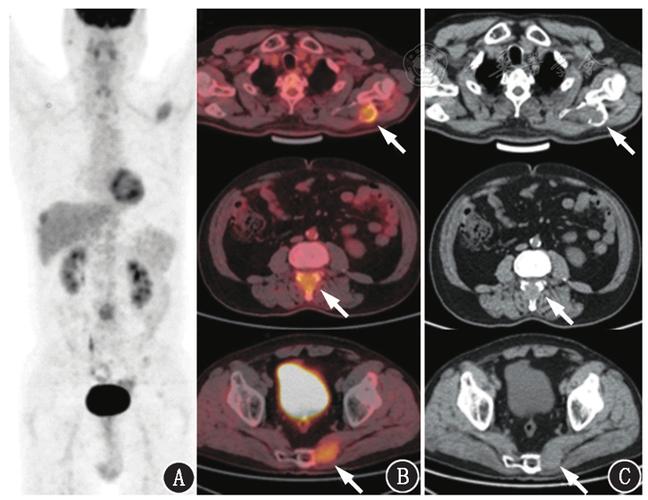

如何看懂petct影像图片,petct图片怎么看肿瘤

【积医科普】带您了解一扫而知全身的pet/ct检查

西安高尚医学影像:pet/ct在肿瘤治疗决策中的应用

petct是什么检查,派特ct能检查什么,派特ct能查出哪些

影像干货 | 核医学(18)f-fdg pet/ct报告书写规范

骨多发病变pet/ct鉴别诊断一例

petct图片怎么看肿瘤